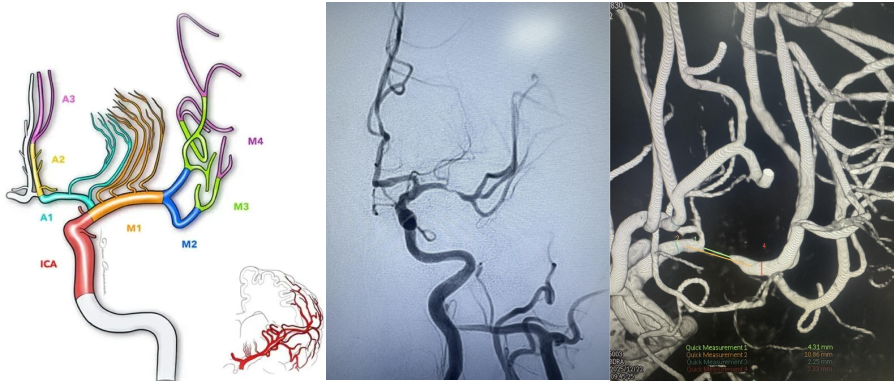

近两个月,61岁的吴先生出现了两次言语含糊不清且右手无力的状况,但幸好未遗留大的后遗症。为何这样说呢?我们看这张图。

大脑中动脉的直径平均为2.7mm,更细者可达到1.5mm,血管狭窄不完全可怕,可怕的是远端血流受限缺血,其上发出的一丛丛小血管常常是导致脑梗塞或脑出血的元凶。吴先生大脑中动脉重度狭窄但还没有完全闭塞,提醒了他两次,就是为了让他能意识到并消除掉这些危险因素。

精准操作!在2.25毫米的血管内“起舞”

颅内血管纤细且脆弱,正常血管也只有2.25毫米,在重度狭窄的颅内血管内放置支架是一项严峻挑战。郭宗培、陈历、熊建医生、聂毅医生团队,身披重达15斤的铅衣,操控堪比头发丝样的导丝,球囊适度扩张狭窄血管,精准释放颅内药物涂层支架,使血管狭窄解除,远端血管再次丰富充盈,为减少以后发生脑梗塞的可能性打下坚实基础。整个过程需要团队的团结紧密协作,这场手术考验的是医生的整体医疗素质。